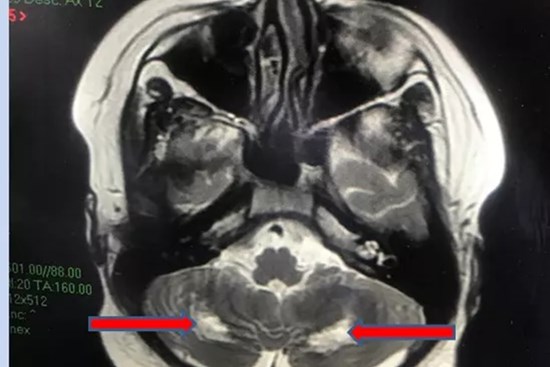

Mắc Covid-19, một học sinh bị tổn thương thần kinh

Đây là trường hợp hiếm gặp khi F0 trẻ em bị tổn thương gan, sau đó bị tổn thương tiểu não.